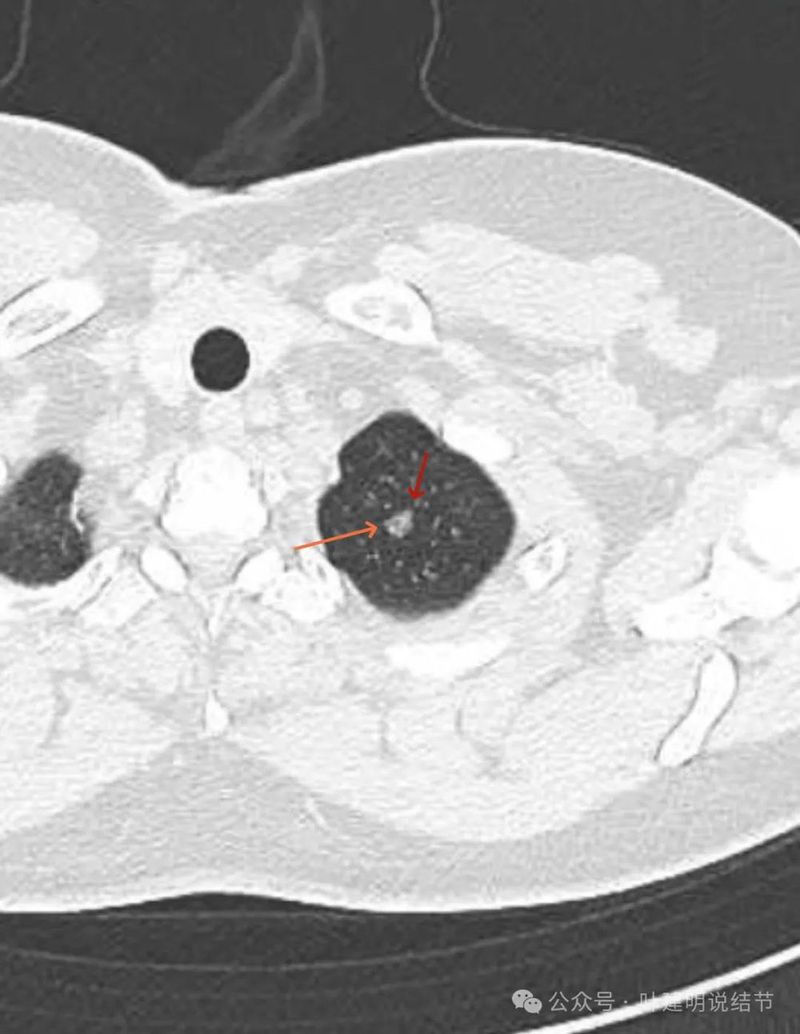

灶内见到血管穿行,整体轮廓清楚,密度欠均。